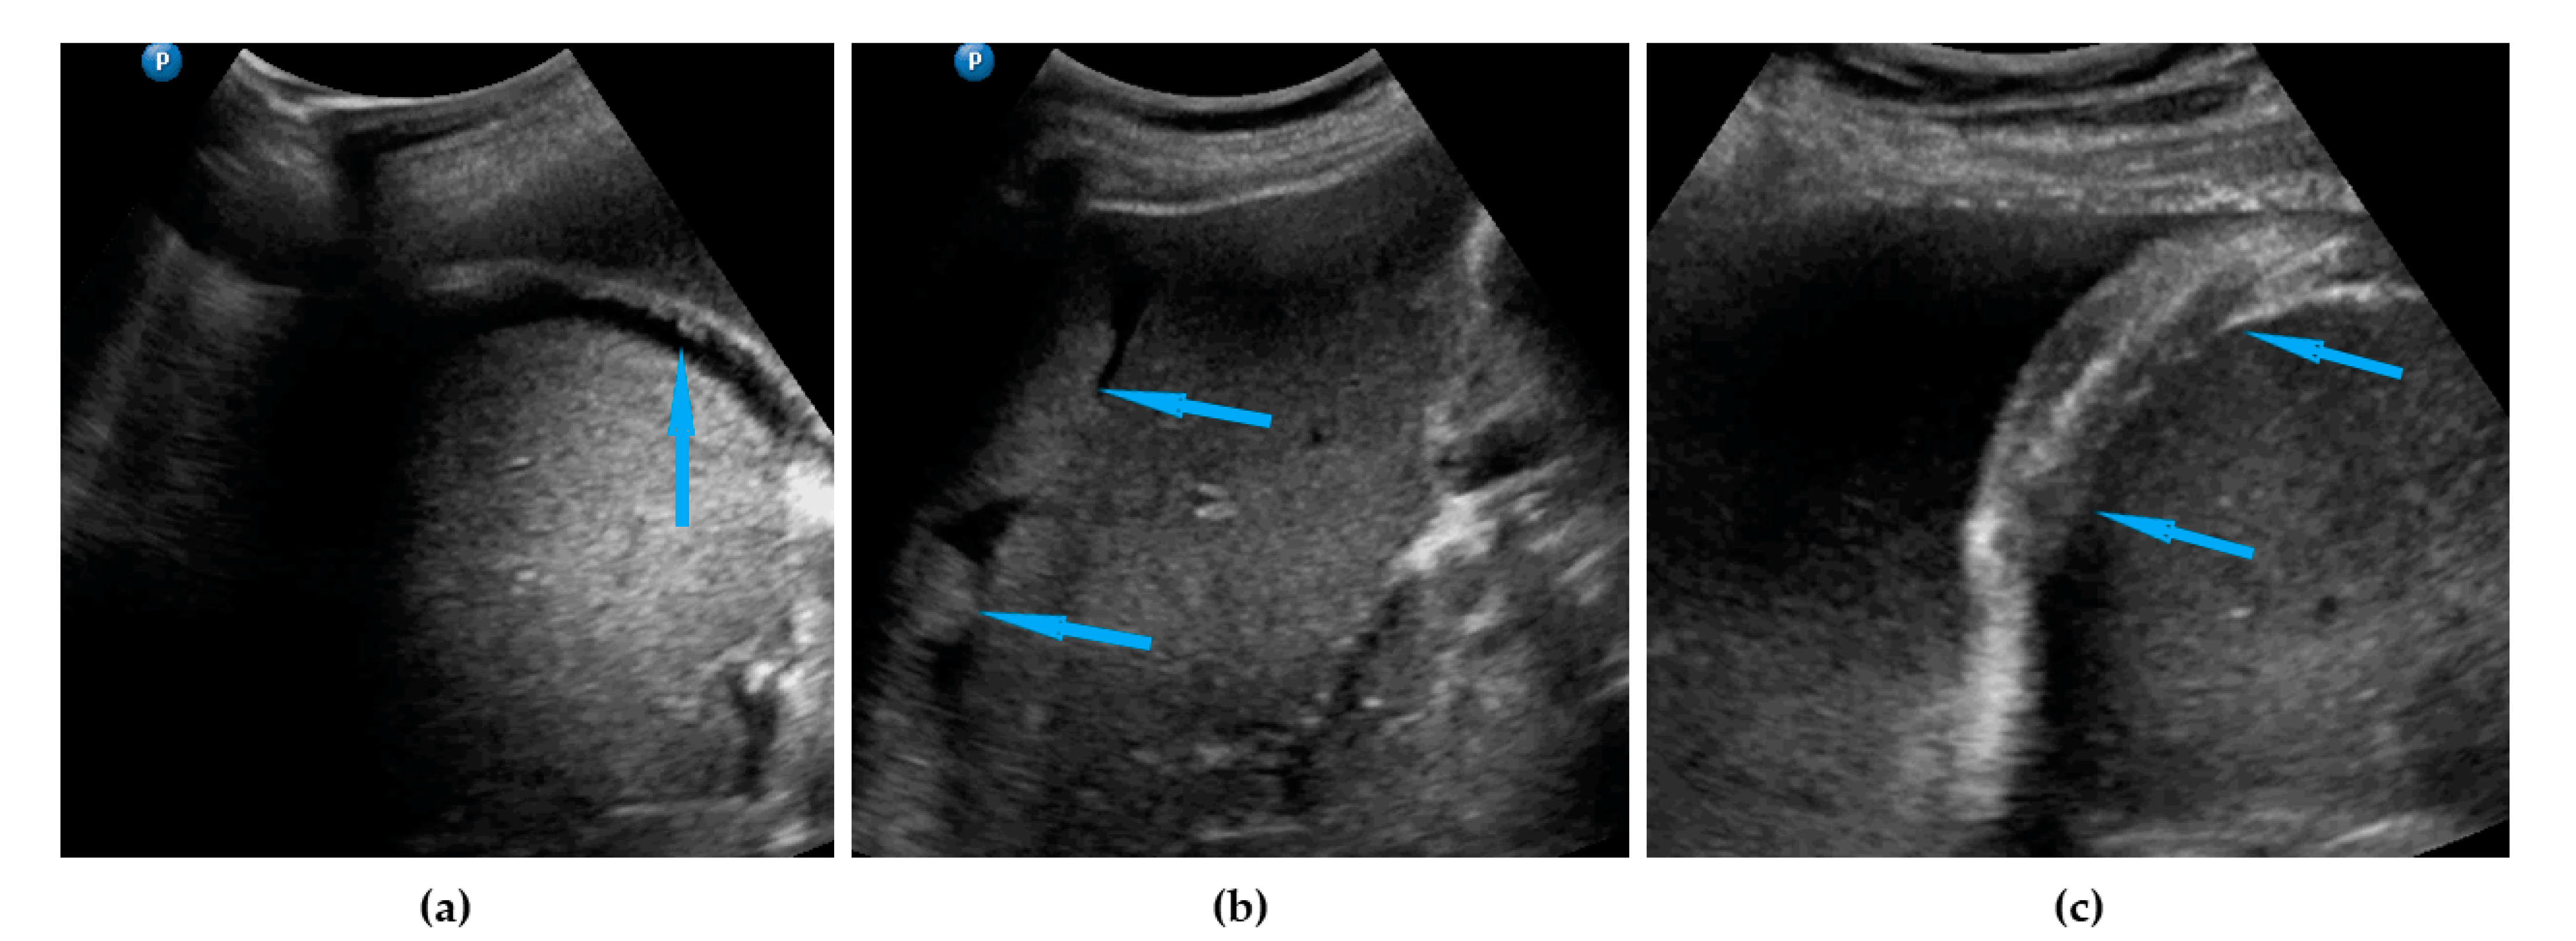

| Liver, parenchymal lesions | Single or multiple focal parenchymal lesions (with a “halo“ sign, necrosis, and indistinct borders) in the liver. | Figure 6 | Video S6 |

| Liver hilum | Presence of nodules or rigid structures in the region of the hepatic hilum. | Figure 7 | Video S7 |

| Spleen, parenchymal lesions | Single or multiple focal parenchymal lesions (with a “halo“ sign, necrosis, and indistinct borders) in the spleen. | Figure 8 | Video S8 |

| Spleen, hilum | Presence of nodules or rigid structures in the region of the spleen hilum. | Figure 9 | Video S9 |